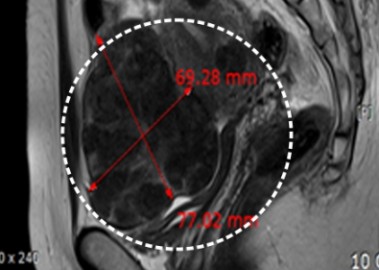

자궁근종 6cm 치료 전후

거대 자궁선근증 치료 사례

장막하근종 치료 사례

다발성 자궁근종 치료 사례

점막하근종 치료사례